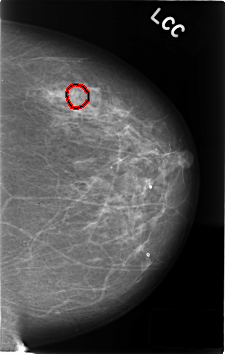

C_0408_1.LEFT_CC

LEFT_CC LINES 4592 PIXELS_PER_LINE 2920 BITS_PER_PIXEL 12 RESOLUTION 50 OVERLAY

FILE: C_0408_1.LEFT_CC.OVERLAY

TOTAL_ABNORMALITIES 1

ABNORMALITY 1

LESION_TYPE CALCIFICATION TYPE AMORPHOUS DISTRIBUTION CLUSTERED

ASSESSMENT 4

SUBTLETY 1

PATHOLOGY BENIGN

TOTAL_OUTLINES 1

BOUNDARY